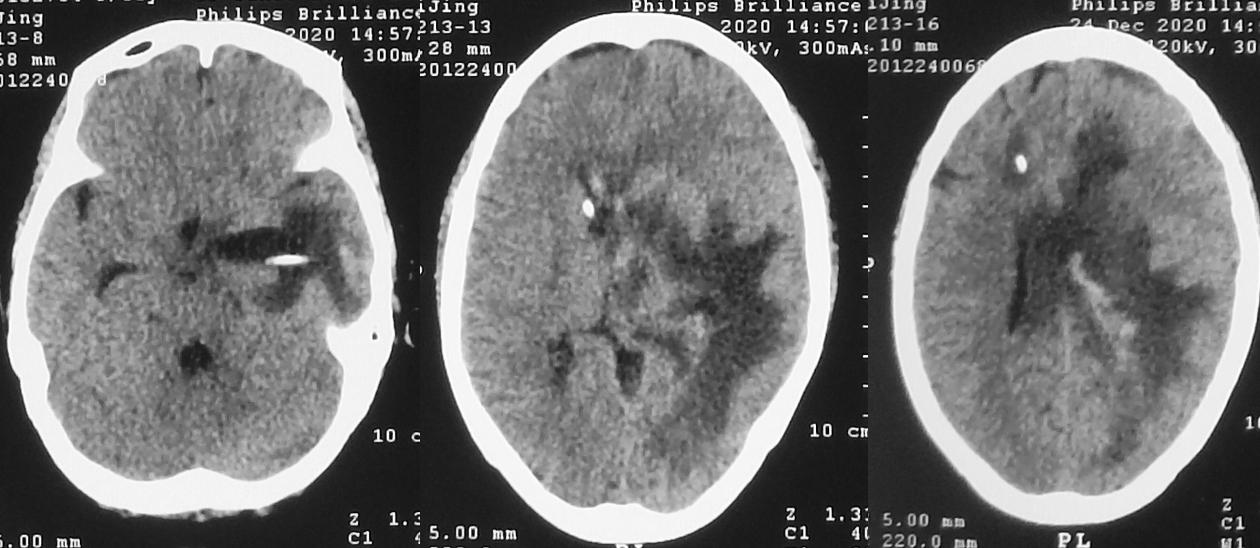

脑脓肿清除术后第23天,拔除外左侧脑室颞角引流管后第6天,即2020年12月31日,患者再次出现昏迷,复查头颅CT( 图-20 )见左侧脑室颞角扩张,右侧脑室引流管脱出。当天再次行左颞角穿刺引流术,同时调整右侧脑室引流管深度后引流通畅。

图-20: 2020年12月31日头CT

第二次左侧颞角引流术后第1天,即2021年1月1日,患者神志明显好转,清醒,可遵嘱动作,复查头颅CT见各脑室较前均缩小( 图-21 )。

图-21: 2021年1月1日头CT